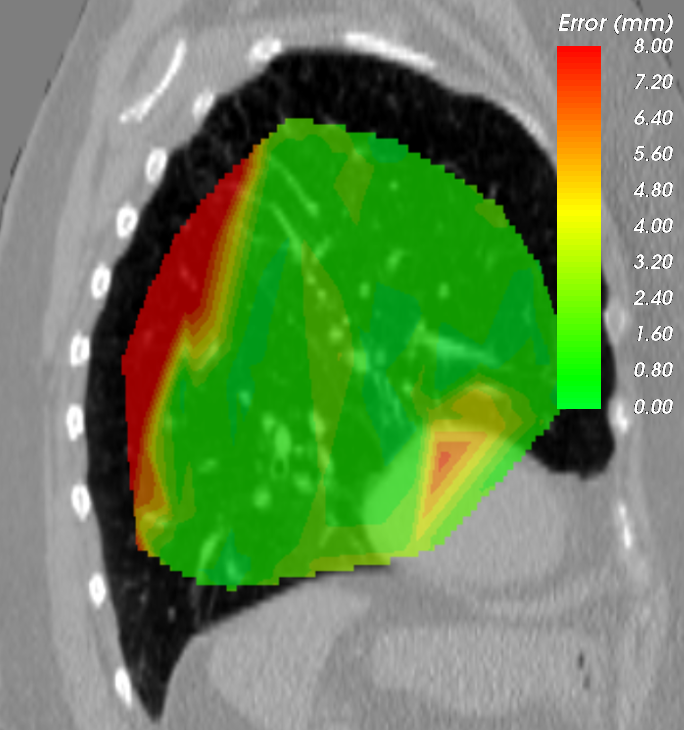

Refer to caption a) DirLab08 deformation grid for inhale to exhale registration Refer to caption b) DirLab08 with overlayed image foldings (Jacobi determinant << 0) Refer to caption c) DirLab08 registration error

Figure 5: This figures show an analysis for two test cases that resulted in the worst results for 3D registration evaluation. The first row shows the extreme inhale phase of dataset Dirlab08 with overlayed deformation grid (a), Jacobi determinant (b) and registration error (c). The patient had a very strong sheering motion along the ribcage in caudal direction which could not be fully captured by our network. The second row shows the extreme diastolic phase for the dataset SC-N-3 with overlayed deformation grid (d) and Jacobi determinant (e) and the extreme systolic phase with contours of the left ventricle (f).